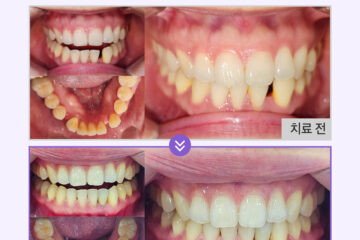

환자분은 잔존한 치아가 얼마 남지 않았지만

그 치아들마저도 치조골 소실로

흔들리는 상태였으며,

전치부만을 사용하여 식사하다 보니

영양소의 섭취도 제대로

이루어지지 않는다고 하셨어요.

나머지 치아들은 모두 발치가 진행되어야 했으며,

하악에 식립 되어 있는 하나의 임플란트에도

염증이 발생되어 있어 함께 제거하기로 했어요.

환자분께서는 뼈이식 없이

상악 6개, 하악 6개의

연제구임플란트를 식립하여 총 28개의

치아 기능을 회복하였고,

홀쭉하게 들어갔던 볼도

펴진 모습을 보실 수 있는데요.

진작 하실 걸 그랬다며 높은 만족감을 가지고 사용 중이세요.